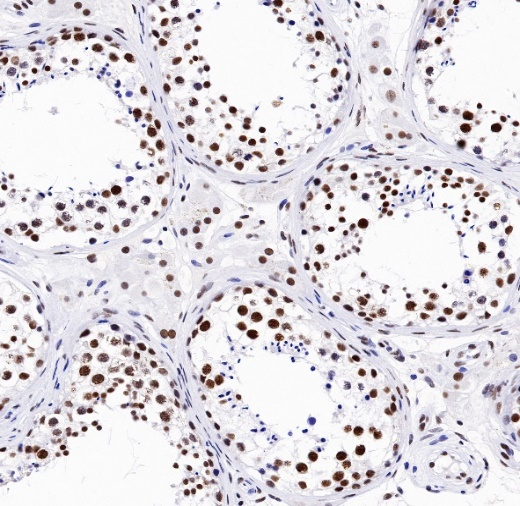

IHC shows positive staining in paraffin-embedded human testis. Anti- TDP-43 antibody was used at 1/1000 dilution, followed by a HRP Polymer for Mouse & Rabbit IgG (ready to use). Counterstained with hematoxylin. Heat mediated antigen retrieval with Tris/EDTA buffer pH9.0 was performed before commencing with IHC staining protocol.